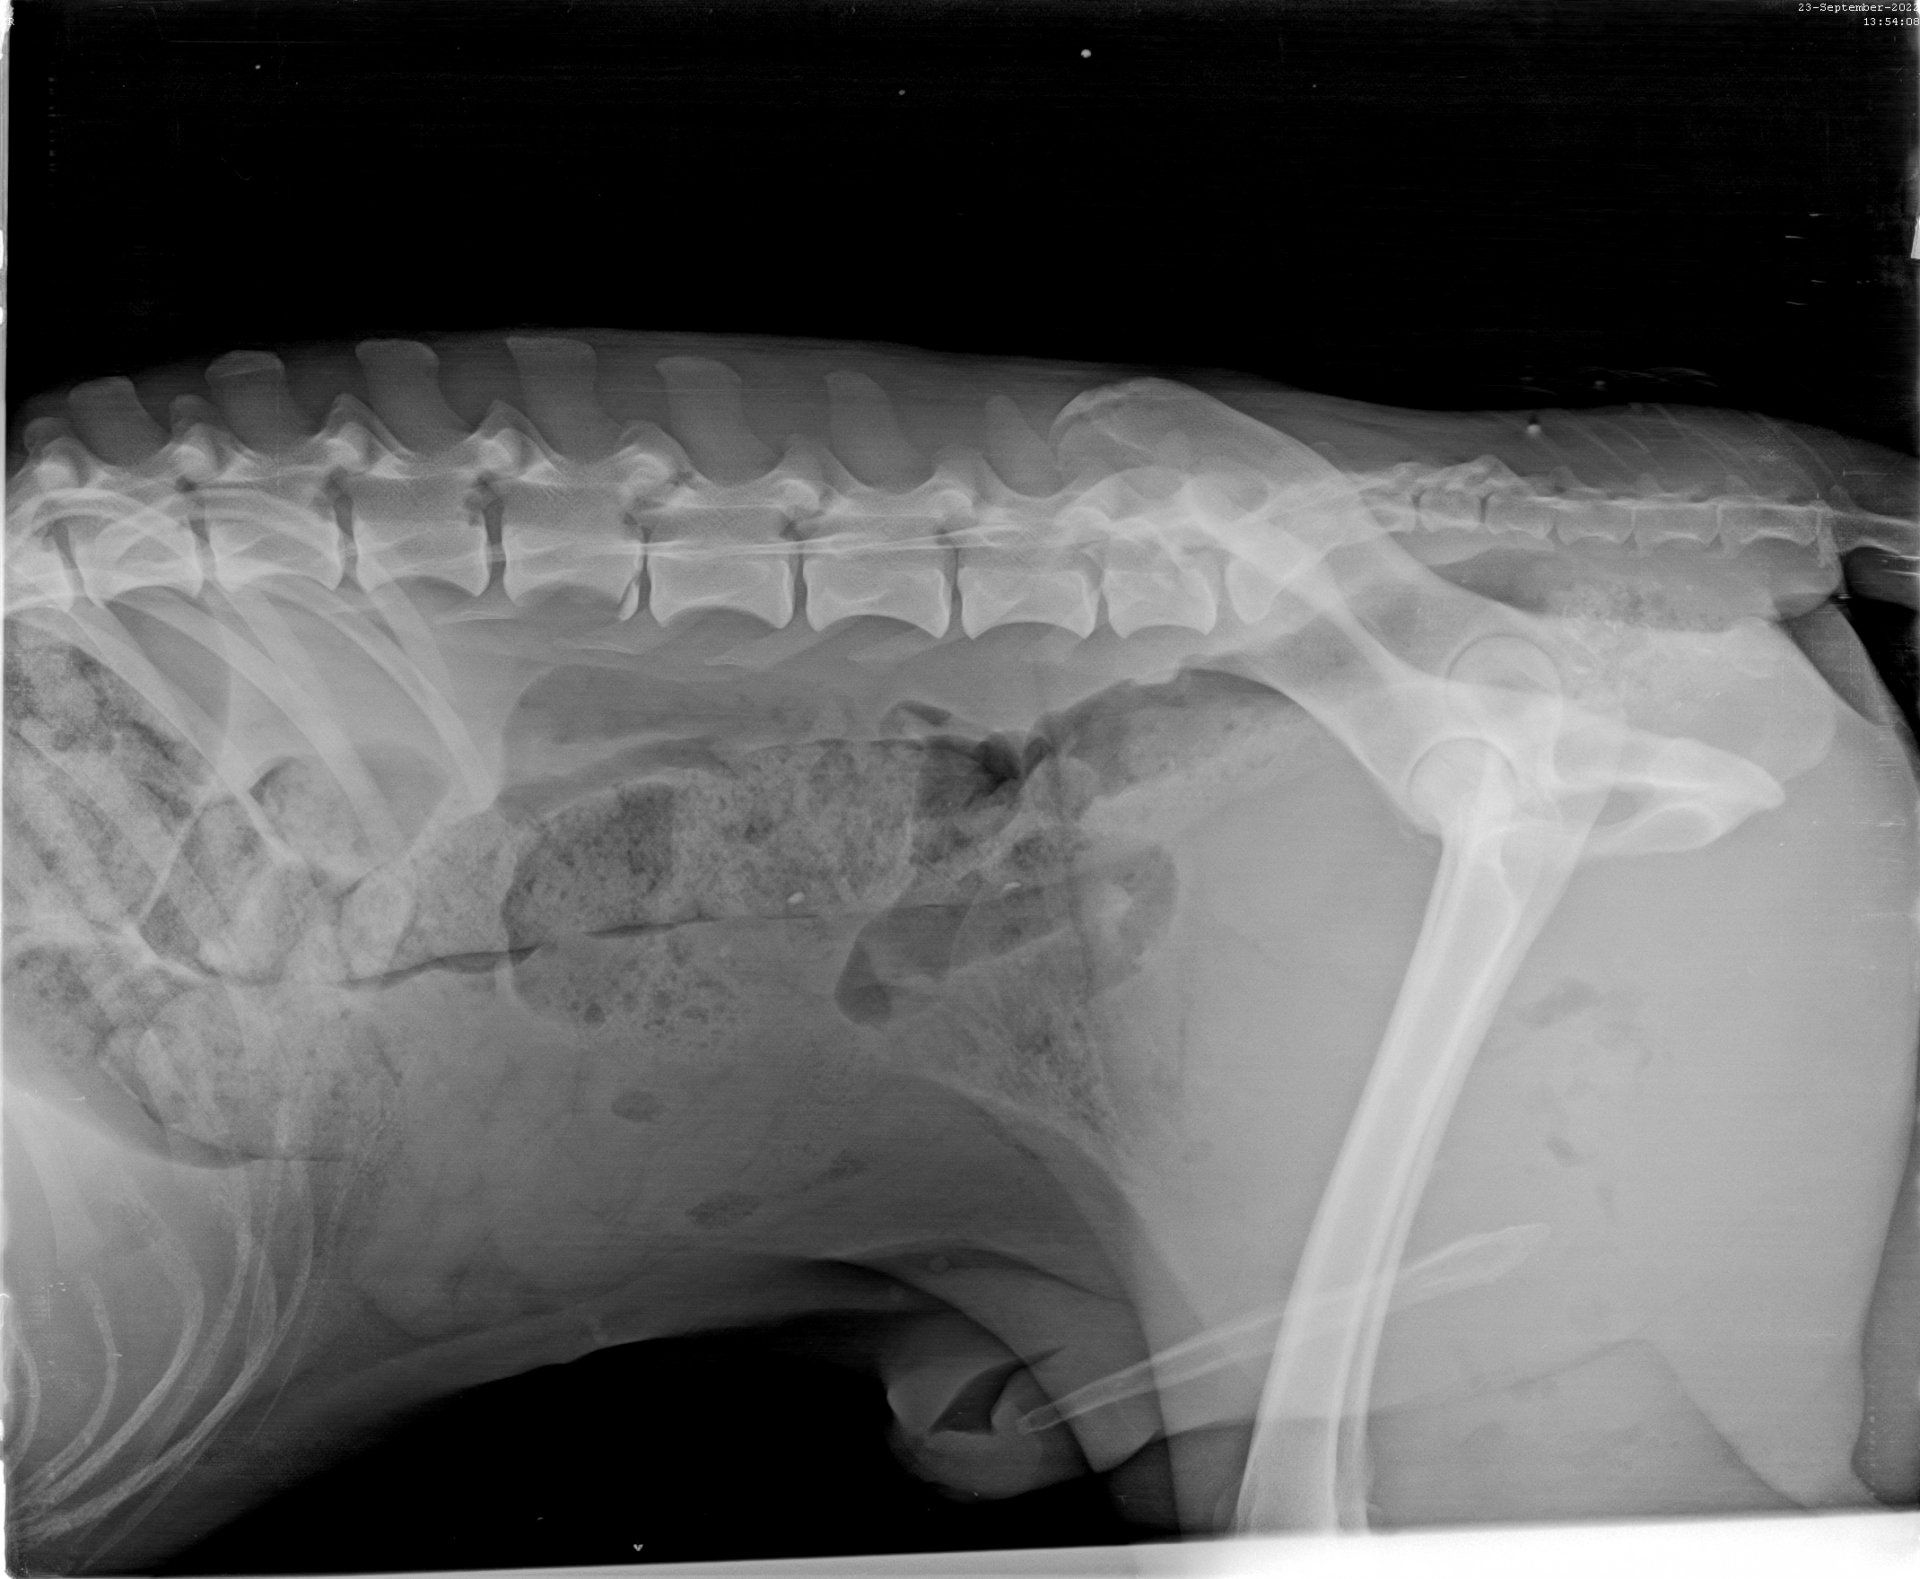

Der Klinikbericht zu der kleinen blinden Hündin ist da:

VETERINARY CLINIC Thessaloniki

„REPORT" Der Hund namens Nike wurde am 21/09/2022 mit neurologischen Symptomen vorgestellt: Ataxie, Desorientierung, Muskelzittern und unsicherer Gang. Nach der neurologischen Untersuchung wurde eine Erkrankung des Vorderhirns vermutet. Die Blutuntersuchung war innerhalb normaler Grenzen. Die Liquor-Analyse ergab keinen Hinweis auf eine Infektionskrankheit oder eine auf Steroide ansprechende Meningoenzephalitis. Es wird ein MRT des Gehirns und eine neurologische Untersuchung durch einen Facharzt für Neurologie empfohlen, um eine angeborene Hirnerkrankung zu bestätigen und die Prognose zu bestätigen. Die Untersuchungen von Nike sind beigefügt (s.Bilder)“

Diese Untersuchung (MRT) würden wir gern machen lassen, denn Nike hat ein Recht zu leben. Nur so können wir sie optimal fördern. Wir suchen also Paten, die mit uns für die kleine Kämpferin sorgen wollen. Bitte helft Nike!!!